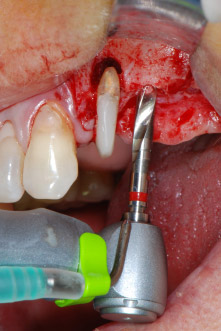

En el siguiente paso, los lechos del implante se prepararon en las posiciones 25 y 26 con instrumentos rotatorios, utilizando un contra-ángulo con un coeficiente de transmisión de 20:1 (WS-75 L, W&H), junto con el nuevo potente motor de implantes Implantmed de W&H (figuras 8 y 19).

La preparación final junto al seno se realizó de nuevo con un inserto piezoeléctrico (Piezomed S2).

El lecho del implante se preparó con el nuevo motor de implantes Implantmed de W&H, en combinación con un contra-ángulo específicamente diseñado para cirugía oral e implantología.

El coeficiente de transmisión de 20:1, junto con el alto torque de hasta 6,2 Ncm del motor de implantes, permite una preparación a baja velocidad, así como la inserción del implante y el corte de roscas. La preparación final hasta la membrana del seno se realizó de nuevo con la unidad piezoeléctrica y un inserto de diamante redondo (Piezomed S2 de W&H).